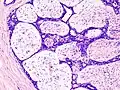

Histopathologic image of breast fibroadenoma showing proliferation of intralobular stroma compressing and distorting the epithelium. H&E stain. -

Fibroadenoma of the breast is a benign tumor composed of a biplastic proliferation of both stromal and epithelial components.[12][13] This biplasia can be arranged in two growth patterns: pericanalicular (stromal proliferation around epithelial structures) and intracanalicular (stromal proliferation compressing the epithelial structures into slit-like spaces).

These tumors characteristically display hypovascular stroma compared to malignant neoplasms.[2][14][9] Furthermore, the epithelial proliferation appears in a single terminal ductal unit and describes duct-like spaces surrounded by a fibroblastic stroma. The basement membrane is intact.[15]